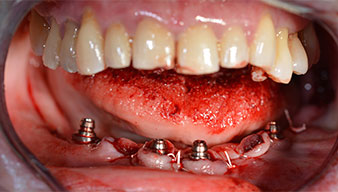

Para la planificación y la minimización del riesgo, se realizó una tomografía volumétrica tridimensional (TVD, Planmeca) que mostró que la calidad y la cantidad del tejido óseo era suficiente para la intervención quirúrgica y el tratamiento inmediato con el método Fast & Fixed. Siguiendo el protocolo de este método, se insertaron los implantes en la región de las piezas 35, 32, 42 y 45. Debido a la inclinación de hasta 45 grados de los implantes distales, el perfil de emergencia se desplazó hacia posterior y se generó un mayor polígono de soporte (fig. 3).

Tras la extracción de la dentición residual en el maxilar inferior, se realizó la incisión crestal en la región comprendida entre la pieza dental 37 y la 47.

A continuación, se identificó el agujero mentoniano (foramen mentale) como la estructura anatómica límite y se alisó el cortical de la cresta ósea con la pieza de mano recta y una fresa redonda grande (fig. 4).

Para compensar la divergencia de los implantes distales, se atornillaron pilares acodados (35 grados) de forma que los perfiles de emergencia de todos los implantes quedaran en la posición más vertical posible en relación con la mordida. Este paso es necesario para poder atornillar de forma oclusal el tratamiento provisional y, posteriormente, el definitivo (figs. 15 y 16).